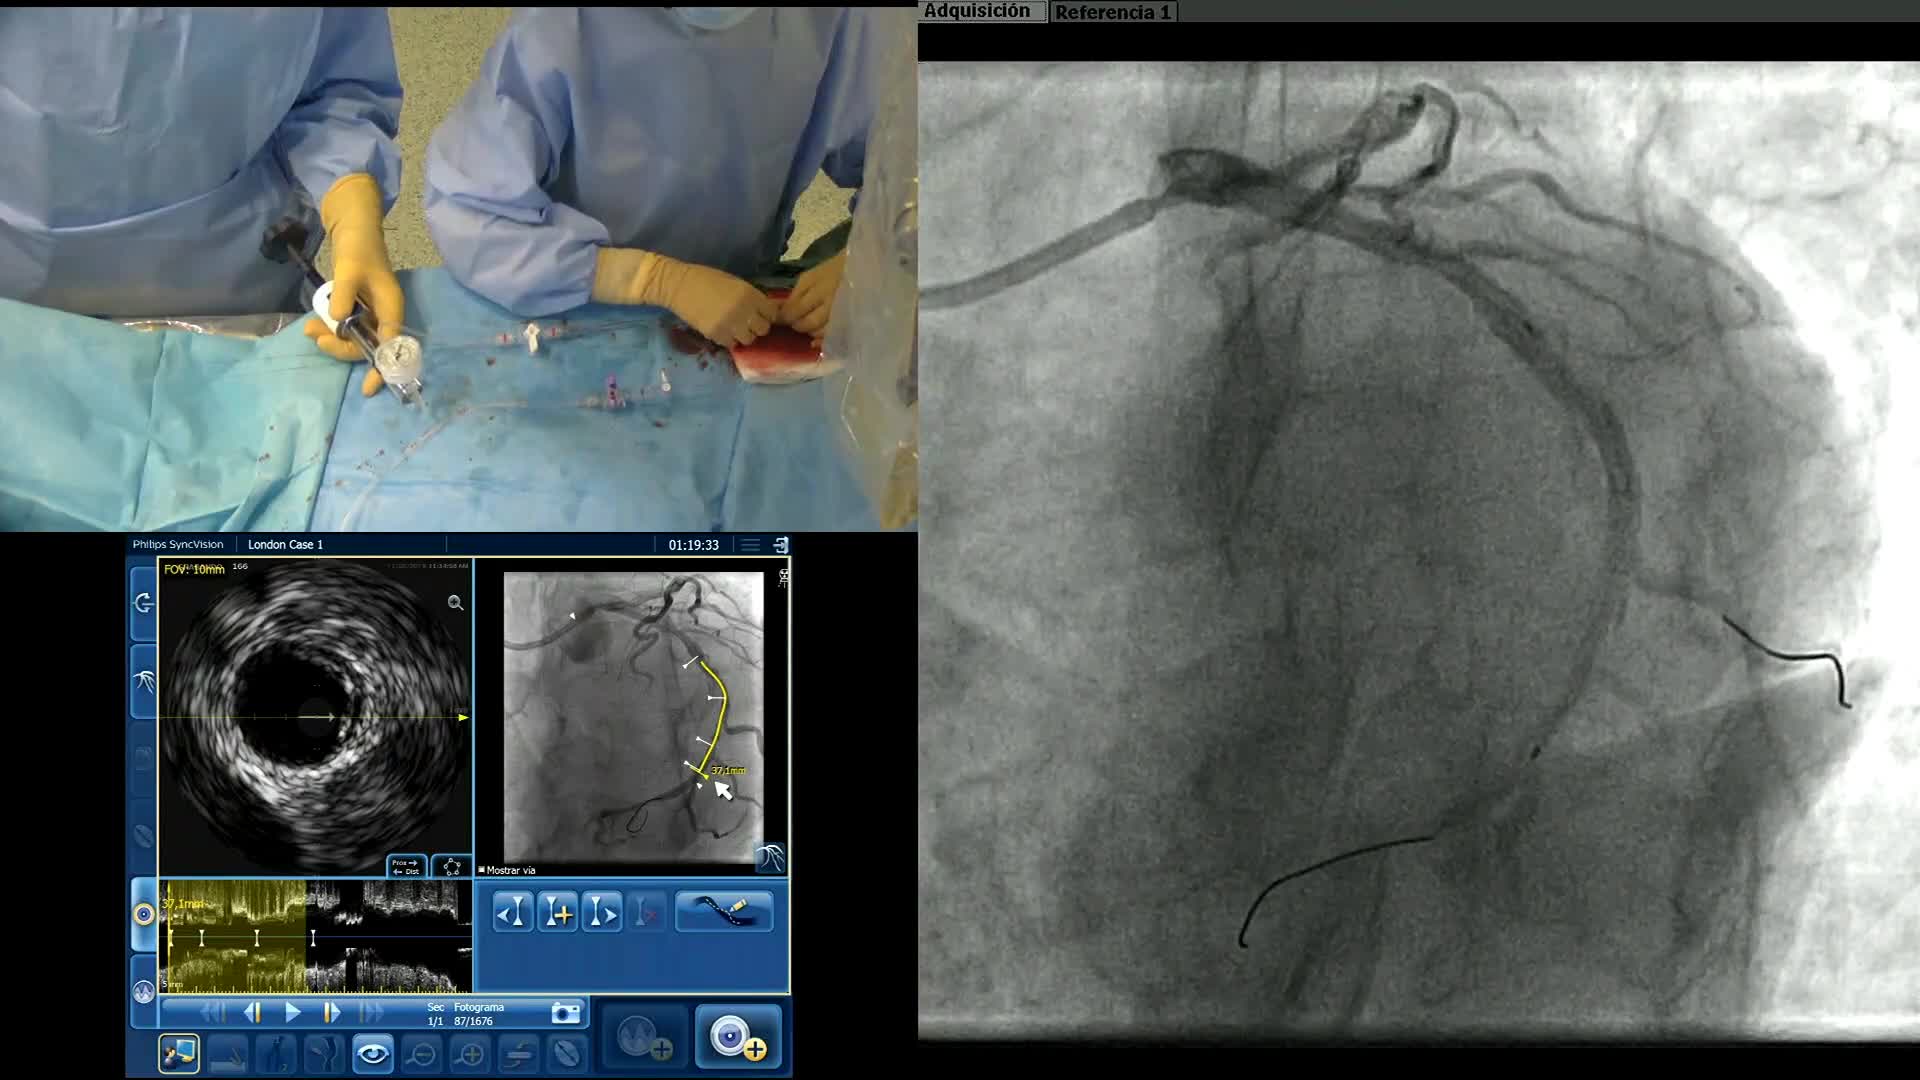

How to perform good co-registration measurements using iFR and IVUS - Dr Allen Jeremias